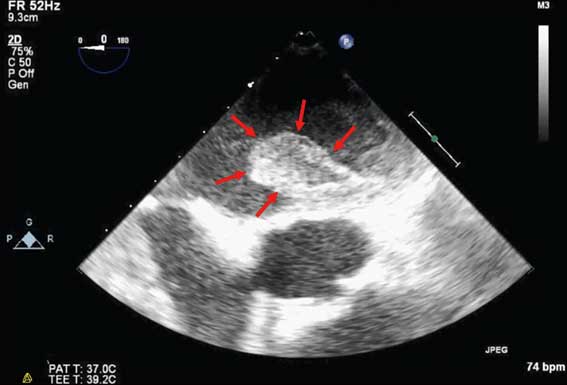

上野 いちばんの問題は心房が痙攣して収縮しなくなるため、血液が滞留し、血の塊「血栓」を形成しやすくなることです。血栓は左心房内にできることが多く、直径2〜3㎝に及びます。このような大きな血栓が心臓から脳に流れ、太い脳動脈に詰まると重篤な脳梗塞「心原性脳塞栓症」を発症します。致死率が高い上、麻痺などの後遺症が残って介助が必要となるケースも多いです。心房細動と診断されたら、ほとんどの場合血栓化を防ぐ抗凝固薬を服用する必要があります。

心臓の超音波画像

心房細動の左心房内血栓(赤矢印)。約3cmの大きさがある